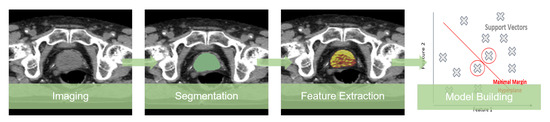

Radiomics, the extraction of quantitative features from medical images using data characterization algorithms, has the potential to provide more relevant information, improve decision outcomes and avoid overdiagnosis and overtreatment. A full radiomic study follows a pipeline initially proposed by Lambin et al. [13] involving several steps, as exemplified in Figure 1.

Figure 1. Radiomic studies pipeline.